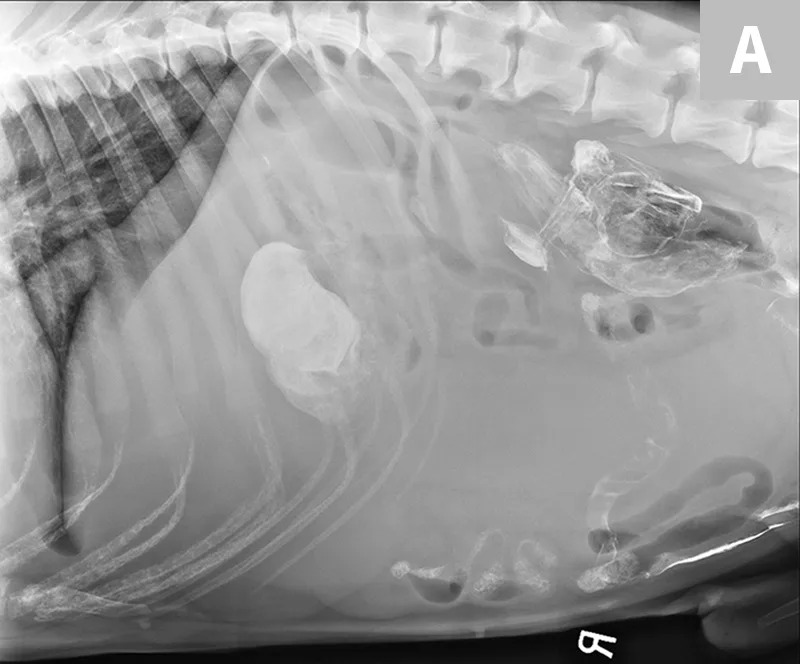

Treatment of the underlying disease in these conditions may relieve or reduce splenomegaly. In cases of splenic torsion (Figures 5 and 6), splenectomy is the recommended treatment, with approximately 90% of dogs surviving to discharge.19

Featured Image

FIGURE 5

Splenic torsion appears as a large soft-tissue opacity that displaces the GI tract caudally and peripherally (A). The splenic head is obscured caudal to the left margin of the stomach (B). The metallic opacity seen in the stomach and intestines is caused by recent barium administration.